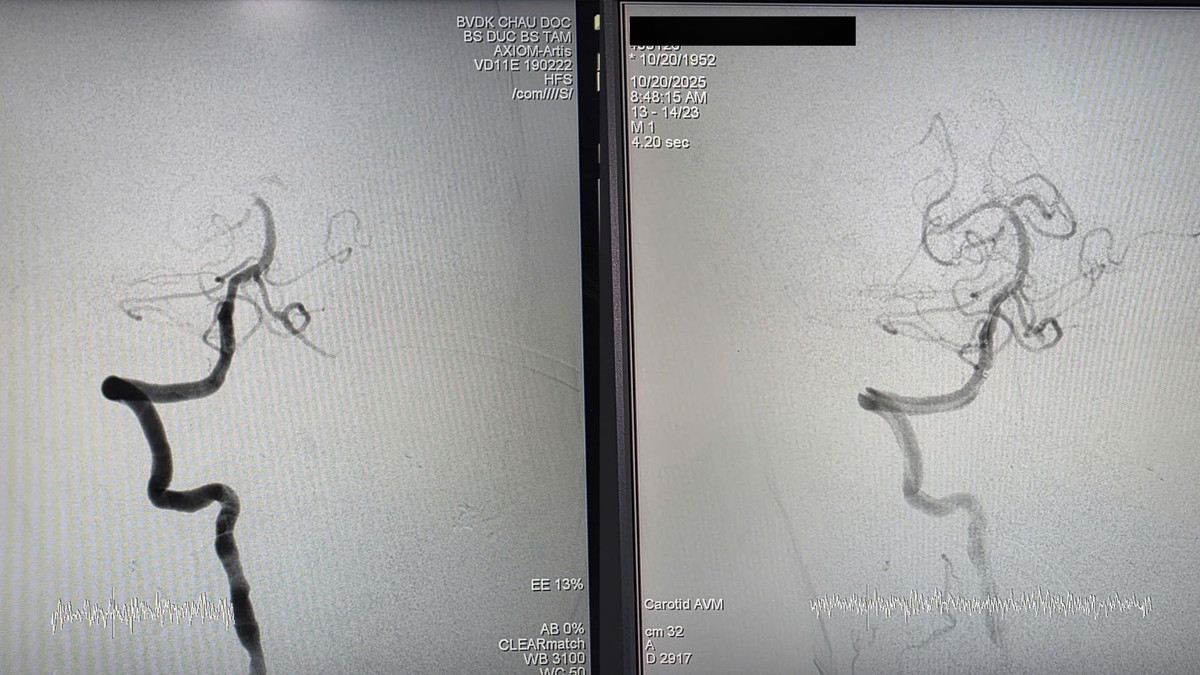

Ngay lập tức, ê-kíp tiến hành can thiệp DSA cấp cứu lấy huyết khối bằng dụng cụ cơ học (EVT) khẩn cấp cho bệnh nhân. Sau can thiệp 1 giờ, tình trạng sức khỏe bệnh nhân phục hồi dần, hết khó thở, phục hồi sức cơ, ngưng thở máy...

Hình ảnh trước và sau can thiệp - Ảnh BVCC